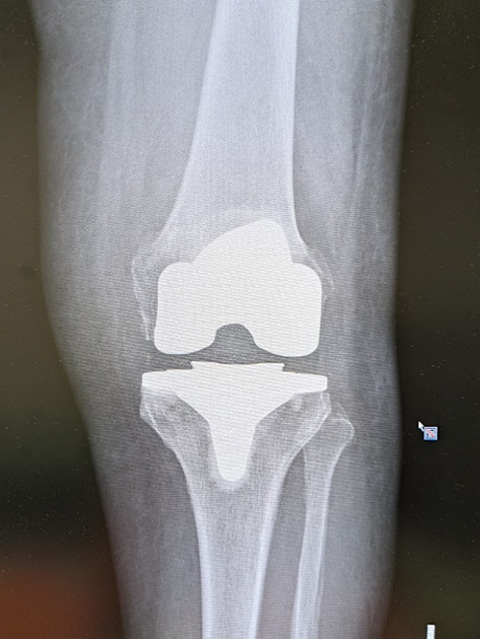

人工膝関節置換術

膝関節の軟骨のすり減りや骨の変形により歩行時の痛みが強い場合に行う手術で、膝の痛んでいる部分を切除し金属に置き替える手術です 痛みの軽減と歩行能力の改善には大きな効果があります 変形が進行し、強い痛みのため日常生活に支障が出ている方に適した治療法です。

高度な変形やリウマチなどに対しは全人工膝関節置換術(TKA)を行います。痛みが膝の内側か外側だけの場合には単顆部膝関節置換術(UKA)行います。

人工膝関節全置換術 (TKA)

• 人工膝関節全置換術 (TKA)

傷んだ膝関節の骨、軟骨を切除して、大腿骨側、脛骨側にそれぞれ人工関節を挿入し関節の機能を再建する手術です。骨を切る際に、骨を切る量を調節してO脚やX脚を矯正します。